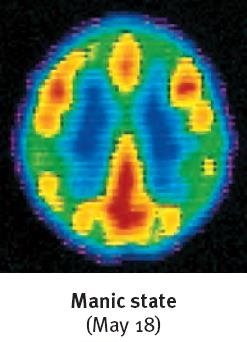

Bipolar Disorder: Alternating episodes of depression and mania (periods of elevated, expansive, or irritable mood, increased energy, impulsivity, and reduced need for sleep). Formerly called "manic-depressive disorder." Mania is more than just a "good mood"—it is a pathological state.

Mania: Exaggerated optimism, hypersociality, impulsivity, racing thoughts, little need for sleep.

Biological Basis of Mood Disorders

Brain imaging studies show that brain activity is diminished in depression and increased in mania. Structural differences include smaller frontal lobes in depression and fewer axons in bipolar disorder. Neurotransmitter imbalances are also implicated: reduced serotonin in depression and increased norepinephrine in mania.